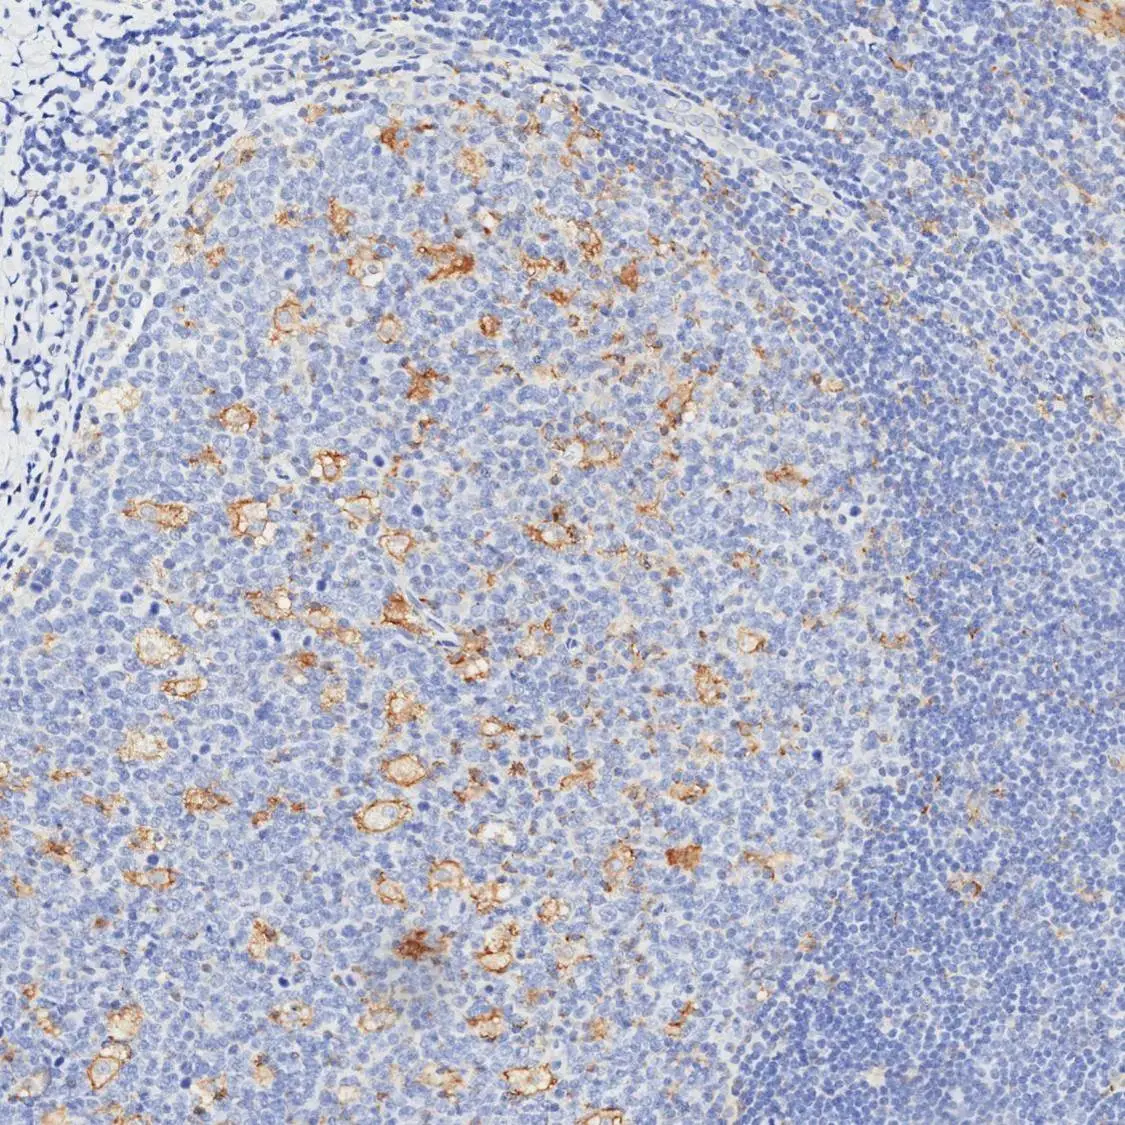

IHC-P analysis of human lymph node tissue using GTX639925 PD-L1 antibody [H302] HistoMAX™.

A subset of inflammatory cells stain PD-L1 positive.